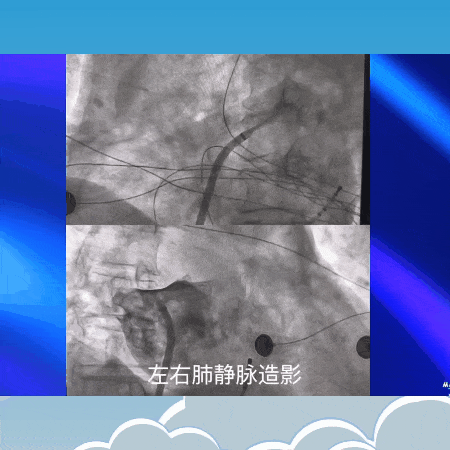

心血管科钱剑锋主任医师应用FARAWAVE脉冲消融系统,对左右肺静脉、左心房顶部和后壁消融(释放高压脉冲电场);

图片

整个手术只用了90分钟,其中真正“消融”(破坏异常心肌)的时间才20分钟! 术中患者生命体征平稳,术后第二天就能下地活动。